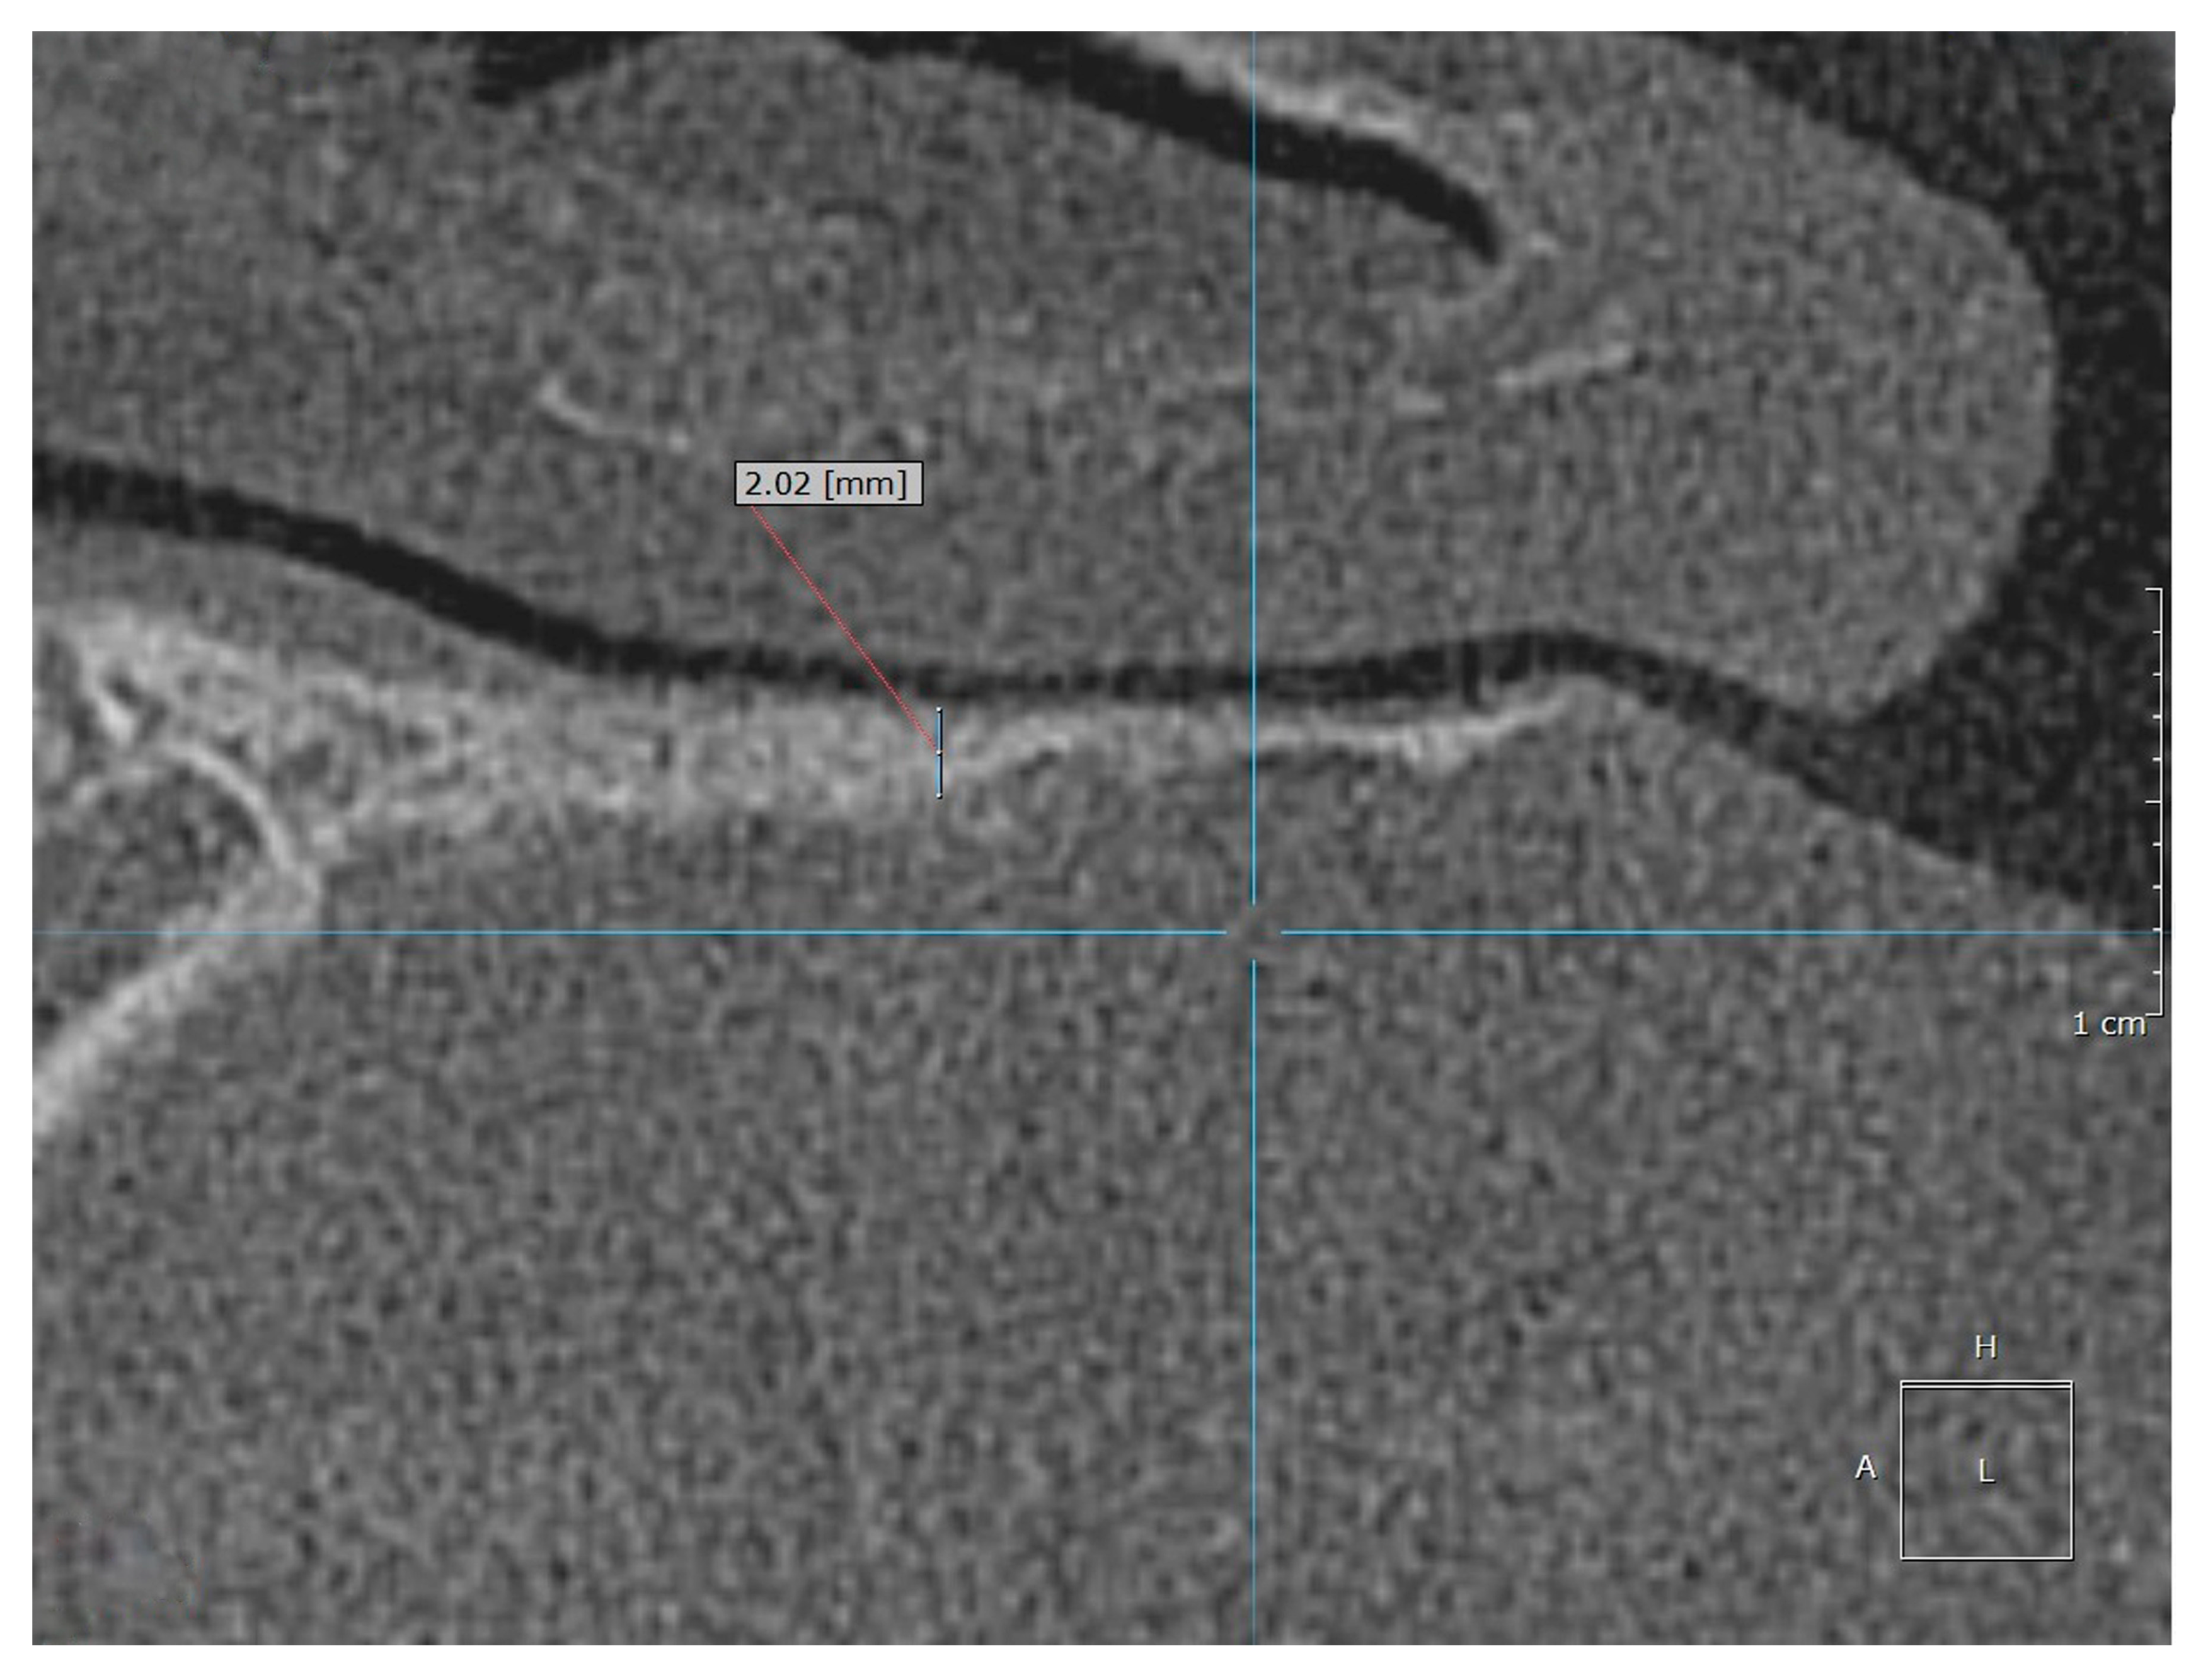

The HPT was measured at maximum magnification in the Picture Archiving and Communication System (=PACS). We defined the measurement point for HPT on the left dorsal third of the palatal process of the maxilla because the contour of the hard palate is linear here over approximately 1 cm (see Figure 1).

Examples of the measurement of normal, osteopenic, and osteoporotic patients are shown in Figure 2, Figure 3 and Figure 4.

The HPT was measured in the CBCT images by a radiologist and a dentist, independently. The defined measurement point (see Figure 1) was applied for 68 CBCT images: 52 normal and young (control group), 4 normal > 30 years old patients with DXA, and 12 patients with osteopenia or osteoporosis with DXA.

Figure 2. Example of the measurement location for a normal patient.